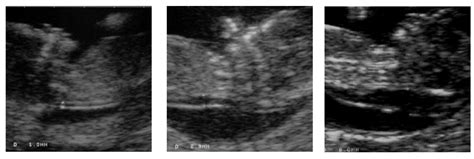

Sprando vaiskumos matmuo (iš kairės į dešinę): 1,3 mm; 2,9 mm ir 6 mm. Šaltinis: babycentre.co.uk